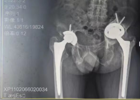

在省人民医院(下称“省人医”)帮扶下,我院骨科医疗技术水平明显提升,近期成功开展了多例关节置换术后翻修术,均取得良好效果。病例一:髋关节置换翻修术患者邝某,男,2022-11-24